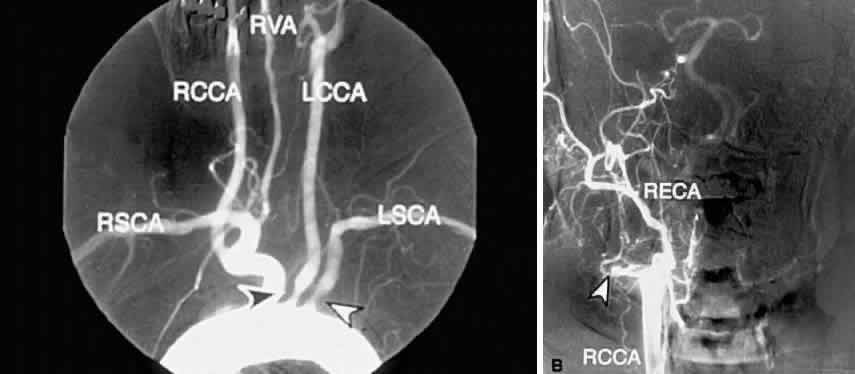

Prolonged arm-to-retina circulation times are frequently observed (Fig. 3B).24 This reflects the slower flow of blood from the carotid artery to the central retinal artery due to carotid occlusive disease. In normal persons, fluorescein dye is first detected in the retinal vasculature 12 to 15 seconds after dye is injected into the arm vein. Uncommonly, dye may take up to 20 seconds to reach the retinal arteries in a normal person. In ocular ischemic syndrome, arm-to-retina circulation times well over 20 seconds are not uncommon. The arm-to-choroid circulation time is also frequently prolonged in ocular ischemic syndrome because of the slow flow of blood from the carotid artery to the short posterior ciliary arteries. In pronounced cases, complete choroidal filling may still be lacking at 1 minute after injection. Accurate measurement of the arm-to-retina or arm-to-choroid circulation times requires experienced fluorescein angiography personnel, and these measurements depend on whether the dye was injected in the antecubital fossa or the hand, the rate of injection, and a reliable timer start time. Delayed or patchy choroidal filling may be seen in 60% of eyes affected with ocular ischemic syndrome (see Fig. 3B; Fig. 3C).1 Normally, the choroid is completely filled within 5 seconds after the initial appearance of dye in the choroid. Patchy choroidal filling greater than 5 seconds reflects sluggish blood flow through the short posterior ciliary arteries. In some cases, one or more quadrants of the choroid may display significantly slower filling than the other quadrants, indicating a relatively lower perfusion of individual short posterior ciliary arteries. Retinal arteriovenous transit time is measured from the initial appearance of dye within the retinal arteries in the temporal vascular arcade until the corresponding veins are completely filled. In normal patients, this occurs within 11 seconds; in ocular ischemic syndrome, the arteriovenous transit time is prolonged in approximately 95% of affected eyes (see Fig. 3B and C; Fig. 3D).1 Although this finding is relatively sensitive for a retinal vascular flow anomaly, it may also be seen in other vascular occlusive disorders, such as arterial and venous occlusive disease. Sometimes, a well-demarcated, leading edge of fluorescein dye within a retinal artery may be seen (Fig. 4B and C). This distinctly abnormal finding is seen in retinal arterial occlusion and ocular ischemic syndrome. In extreme cases of ocular ischemic syndrome, the retinal veins may fail to fill throughout the entire study. Staining of the retinal vessels can be seen in approximately 85% of ocular ischemic syndrome eyes in the later phases of fluorescein angiography (Figs. 4E, 5C, and 6C).1 The arterioles are usually involved to a greater extent than the venules. Hypoxic damage to the endothelial cells and pericytes may account for this phenomenon.11,25 In contrast to ocular ischemic syndrome, fluorescein angiography of eyes with central retinal artery obstruction rarely show late vascular staining. In CRVO, the retinal veins typically stain more than the retinal arteries.

ATHEROSCLEROSIS Atherosclerotic disease, because of its occlusive effects on the carotid arteries, is by far the most common cause of ocular ischemic syndrome. Histologically, there is thickening and hardening of the carotid artery caused by lipid-rich lesions within the innermost vessel layer.49,50 These lesions may partially or completely occlude the artery, either by slow growth or by a more rapid occlusion from hemorrhage into a plaque or thrombus formation. The most common site of atherosclerosis in the neck vessels is at the origin of the internal carotid artery. From this point, the atherosclerosis often propagates downward in a retrograde fashion into the common carotid artery. Less commonly, lesions may occur at the siphon, the S-shaped portion of the internal carotid artery that lies in the cavernous sinus. Rarely, the origin of the common carotid artery is the region affected. There is an association between atherosclerosis and increased levels of plasma lipoprotein, principally low-density lipoproteins.51 Risk factors for atherosclerosis also include cigarette smoking, systemic hypertension, diabetes mellitus, advancing age, male sex, obesity, stress, and type-A personality.52 In addition to its ischemic effects on the eye via carotid occlusion, atherosclerosis is responsible for the majority of cases of cerebrovascular accident and myocardial infarction, and it is therefore the leading cause of death in developed countries. Early diagnosis of ocular ischemic syndrome can therefore reveal underlying atherosclerotic disease in the carotid arteries or other parts of the body. Conversely, evidence of atherosclerotic disease in other parts of the body should raise the possibility of occlusive atherosclerotic carotid disease as well. CEREBROVASCULAR ACCIDENT Cerebrovascular accident, the third leading cause of death in developed countries, is most commonly caused by embolism or thrombus from an atherosclerotic carotid vessel. Thus, the ophthalmologist, in recognizing ocular ischemic syndrome, can play an important role in preventing a stroke by recognizing the effects of atherosclerotic carotid disease on the eye. Conversely, a history of stroke, especially of the middle cerebral circulation, may support a suspicion of ocular ischemic syndrome.53 Internal carotid emboli most commonly affect the middle cerebral artery or its branches, and they may result in paralysis and sensory impairment of the contralateral face, arm, and leg due to damage to the somatic sensory and motor cortices. Central aphasia, word deafness, anomia, jargon speech, sensory agraphia, acalculia, alexia, right-left confusion, and hemineglect may also occur. Homonymous hemianopsia may occur because of damage to the optic radiation deep to the temporal lobe. Paralysis of conjugate gaze to the opposite side may also be seen.54 AORTIC ARCH SYNDROME Aortic arch syndrome describes the clinical picture that results when multiple branches of the aortic arch are affected by a chronic occlusive narrowing of any etiology. Compromised blood flow through the brachial artery causes arm weakness, coldness, and claudications; involvement of the carotid arteries causes symptoms of cerebral or ocular ischemia. When the ophthalmologist encounters signs of ocular ischemia accompanied by symptoms of brachial insufficiency, aortic arch syndrome should be considered as the cause. The most common causes of aortic arch syndrome are Takayasu's arteritis, giant cell arteritis, and atherosclerotic disease affecting multiple branches of the aorta. TAKAYASU'S ARTERITIS Takayasu's arteritis is a rare, chronic inflammatory disease of unknown etiology affecting the large arteries of the body, namely the aortic arch, the descending aorta, the pulmonary artery, and their primary branches. It occurs mainly in young women, and the typical age of onset is 10 to 40 years.55 It appears in all populations, but is more frequently seen in Asians. The early signs and symptoms of Takayasu's arteritis include fatigue, weight loss, low-grade fever, arthralgias, myalgias, and headaches, and it may be mistaken for juvenile rheumatoid arthritis in a young female patient. The later clinical manifestations of Takayasu's arteritis relate to the anatomic site of vascular obstruction. Decreased blood flow to the brachial arteries results in coldness of the hands, paresthesias, and asymmetric or absent brachial pulses.56 Renovascular hypertension develops in half of patients because of involvement of the renal arteries of the abdominal aorta.57 Occlusion or narrowing of the carotid or vertebral arteries may result in cerebrovascular accident.58 Ophthalmic symptoms, due to ocular hypoperfusion from occlusion of the carotid artery, are seen in 15% of cases.59 These ophthalmic changes may be identical to those of ocular ischemic syndrome caused by carotid atherosclerotic disease (see Figs. 5 and 6).60,61 Arteriography of the aortic arch region, showing smooth-walled areas of stenosis and dilation, is usually necessary to confirm the diagnosis (Fig. 11). Collateral circulation, due to the chronicity of the stenosis, is usually prominent.